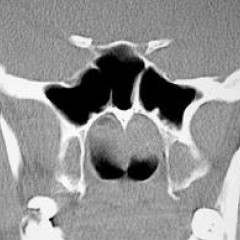

Компьютерная томография

Компьютерная томография позволяет получать более точные и четкие изображения, чем рентгенограммы. Можно оценить форму и структуру носоглоточных миндалин и соседних анатомических образований, построить их трехмерное изображение. Компьютерная томография назначается в тех случаях, когда постановка диагноза по рентгеновским снимкам затруднена, имеются подозрения на другие заболевания.